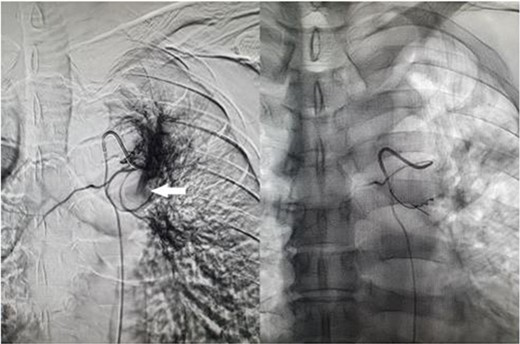

A 57-year-old male presented to the Emergency Department unwell with central chest pain, dyspnoea, and haemoptysis. CT pulmonary angiogram demonstrated bilateral cavitating pneumonia. Irregular nonenhancement of a segmental pulmonary artery in the left upper lobe was also noted (Fig. 1). CT thorax in systemic arterial phase demonstrated enhancement of this segmental branch in the left upper lobe (Fig. 1). These findings are due to reversal of flow in the pulmonary artery branch due to higher pressure blood from the bronchial artery passing through the fistula. The patient was brought to interventional radiology for further investigation and management. An initial nonselective descending aorta angiogram demonstrated the bronchial artery-pulmonary artery fistula in the left upper lobe. Selective cannulation of the enlarged left bronchial artery was then performed followed by microcatheter cannulation of the main feeding vessels to the fistula. The vessels were embolized to stasis with 400-μm microparticles (Embozene 400) and microcoils (Fig. 2). The patient tolerated the procedure well and had an uncomplicated postprocedural course. Pansensitive tuberculosis detected on sputum sample. Treatment with Rifater, pyridoxine, and ethambutol were commenced. No further episodes of haemoptysis have been noted to date on clinical follow-up.

CT pulmonary angiogram (left) demonstrates non-opacifying segmental pulmonary artery (white arrow); on the CT systemic arterial phase angiogram (right), the same segmental pulmonary artery opacifies; background cavitating consolidation is seen in both lungs.